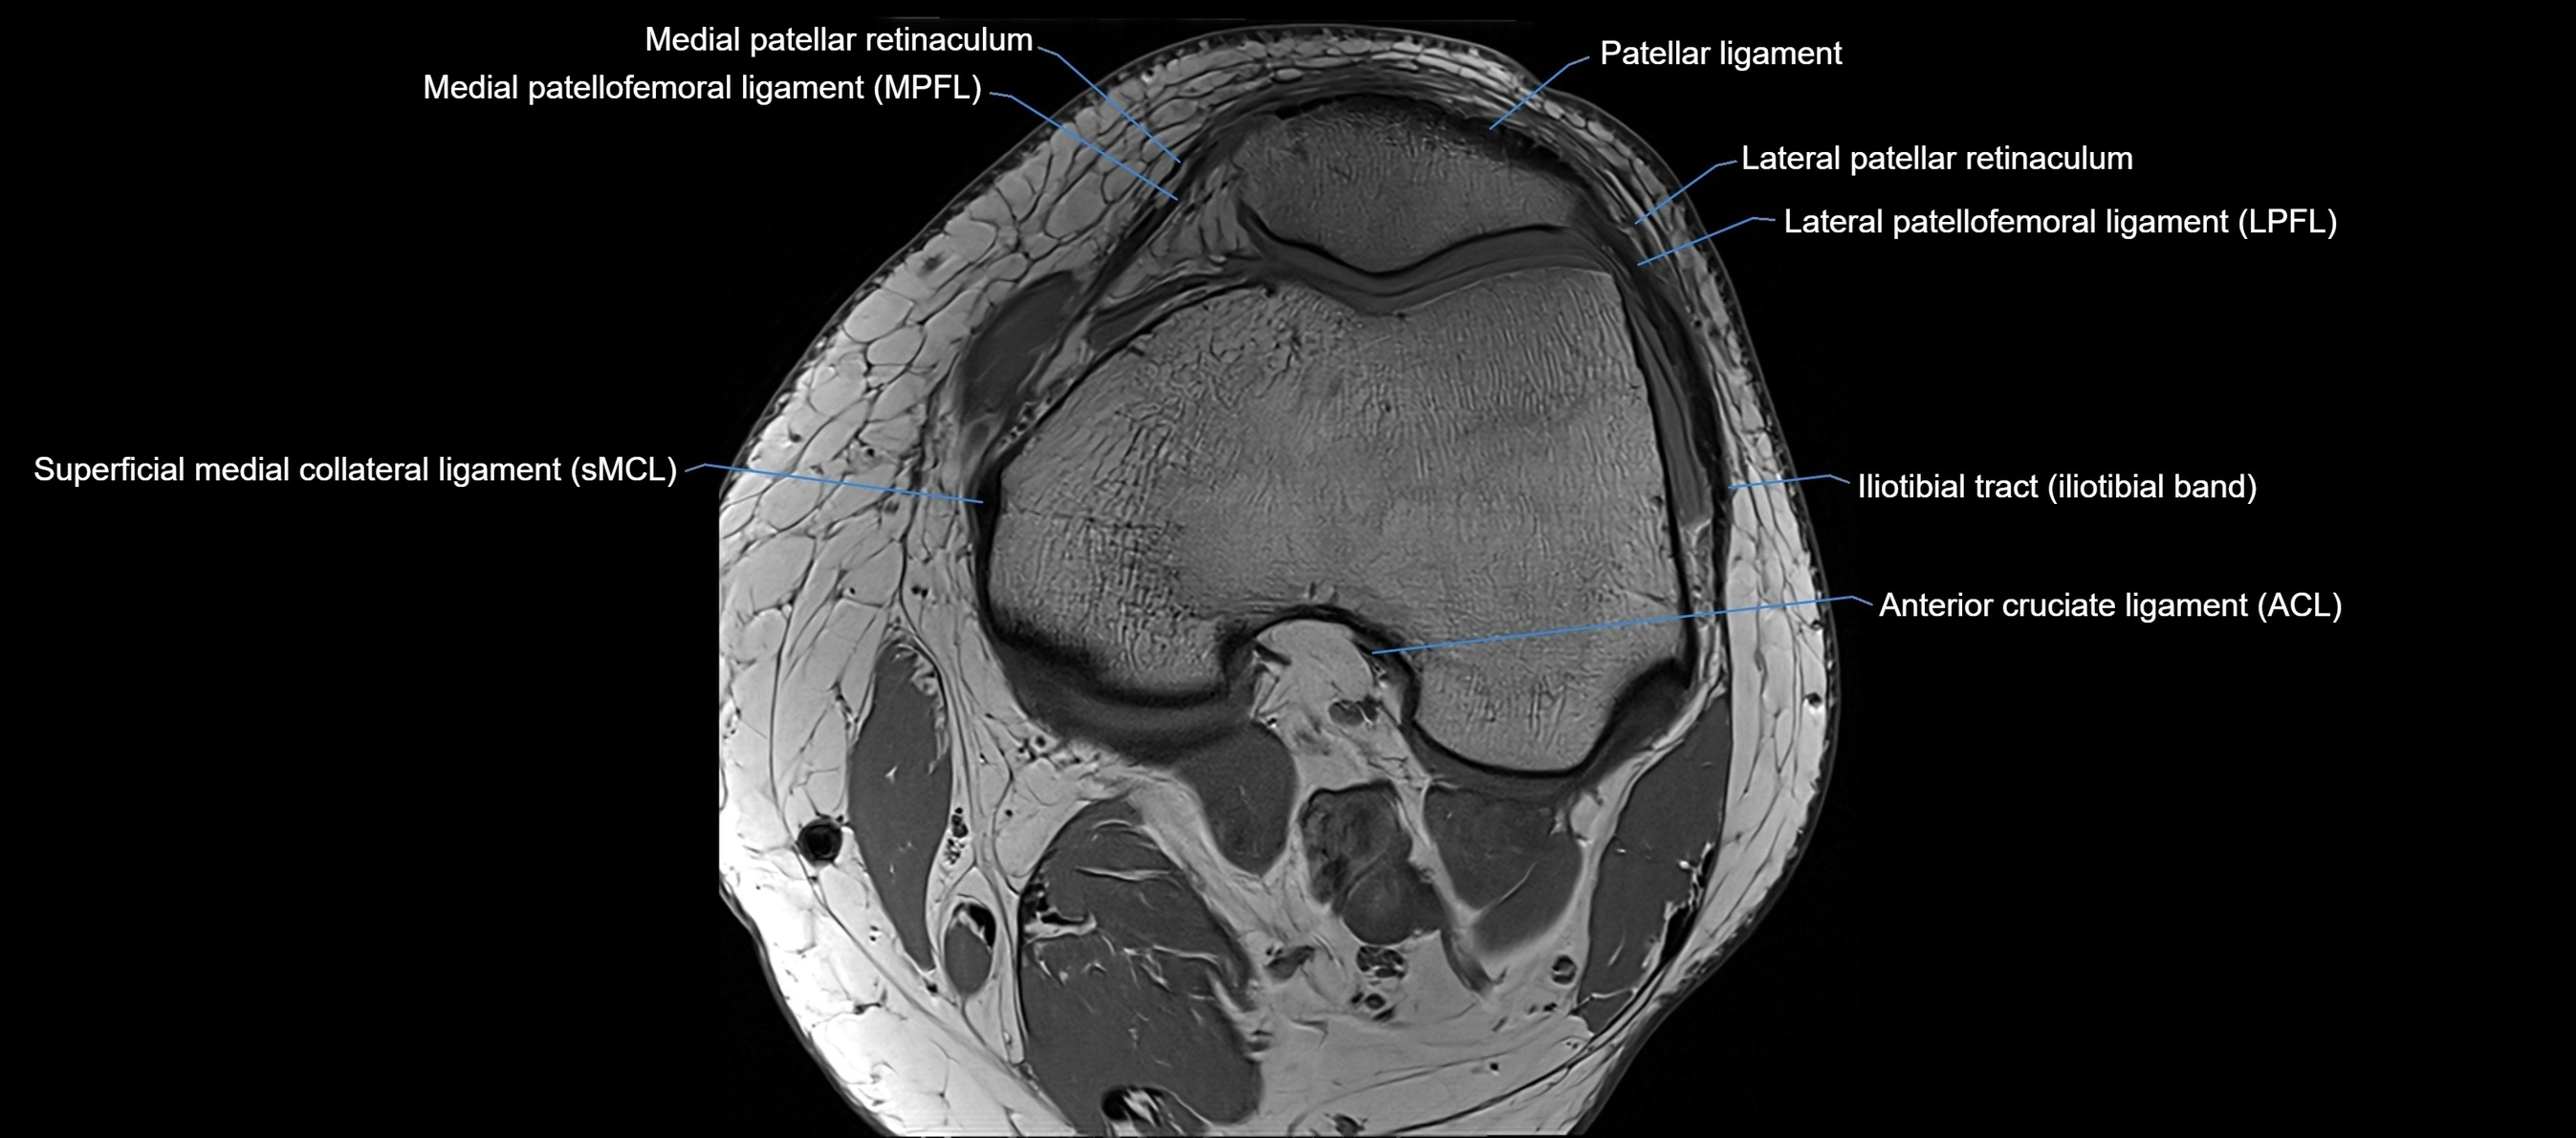

MRI images

image